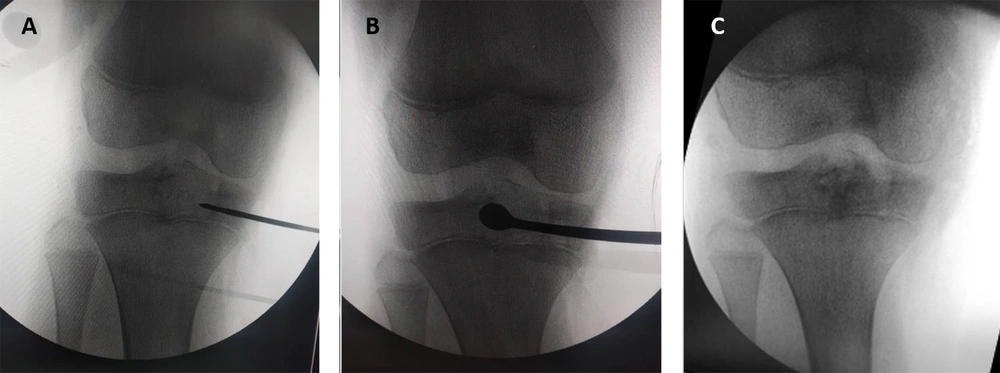

A guide pin was inserted transepiphyseally under fluoroscopic guidance into the center of the lesion. The placement of the guide pin was verified with multiple fluoroscopic views to ensure accurate positioning. Once the guide pin was satisfactorily placed, a 7 mm cannulated reamer was introduced over the guide pin to create a tunnel through the epiphysis, giving access to the centrally located lesion. The 7 mm dimension is less than half of the mean epiphyseal diameter for this age group, ensuring an adequate working channel while preserving the integrity of the epiphyseal bone stock (11). The reaming process was conducted with careful attention to avoid getting through the physis or articular cartilage. Following the tunnel’s creation, the reamer and guide pin were removed. Extensive curettage of the lesion was then performed using a combination of curettes and high-speed burrs. The curettage aimed at removing all visible tumor tissue while preserving the integrity of the surrounding bone structures (Figure 1). Continuous fluoroscopic monitoring was used to ensure thorough removal of the lesion, preventing any violation of the physis or joint space. After achieving adequate curettage, the cavity was irrigated extensively with normal saline to remove any residual tumor cells and debris. In our practice, we have opted not to use any adjuvants due to concerns about potential harm to the physis or articular cartilage. Instead, we utilized calcium phosphate cement products or cancellous bone allografts to fill the defect cavity. The surgical wound was closed in layers. The periosteum was approximated and sutured, followed by closure of the subcutaneous tissue and skin with absorbable sutures. Sterile dressings were applied, and the limb was placed in a well-padded splint to maintain immobilization and reduce postoperative pain and swelling. Partial weight bearing limited to < 15 kg was allowed for the first 6 weeks. Full weight bearing was permitted once radiographs confirmed cortical consolidation, typically at 6 to 8 weeks.